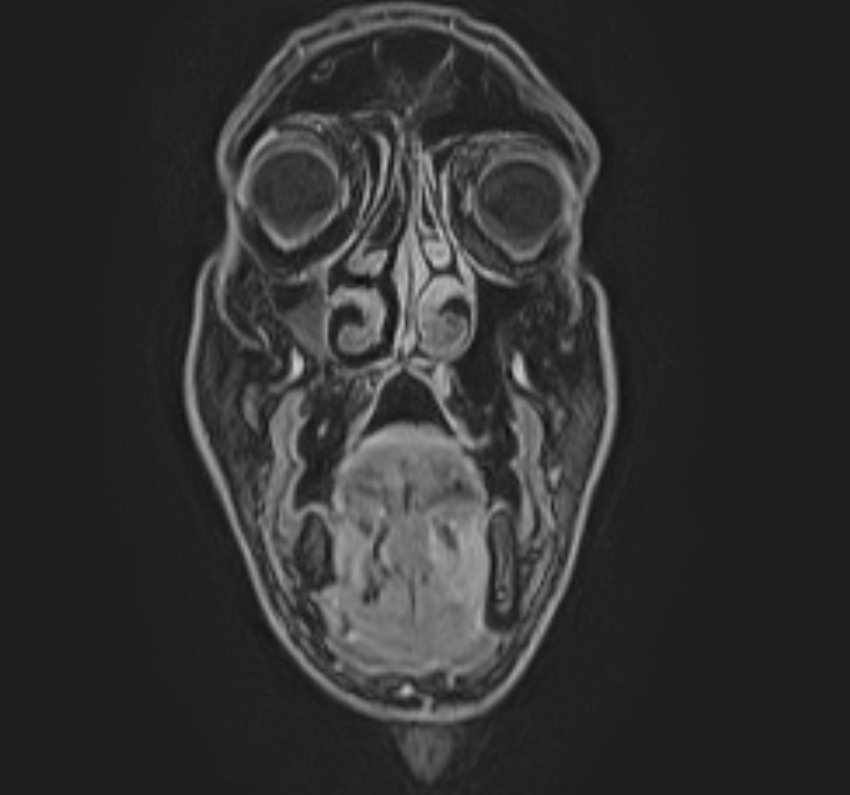

Магнитно-резонансная томография (МРТ) мягких тканей лица – это неинвазивное диагностическое исследование, которое использует магнитное поле и радиоволны для получения детализированных изображений структур мягких тканей в области лица. МРТ мягких тканей лица позволяет визуализировать мышцы, жир, нервы, сосуды и другие мягкотканные структуры, что помогает в диагностике различных заболеваний и патологий, таких как: